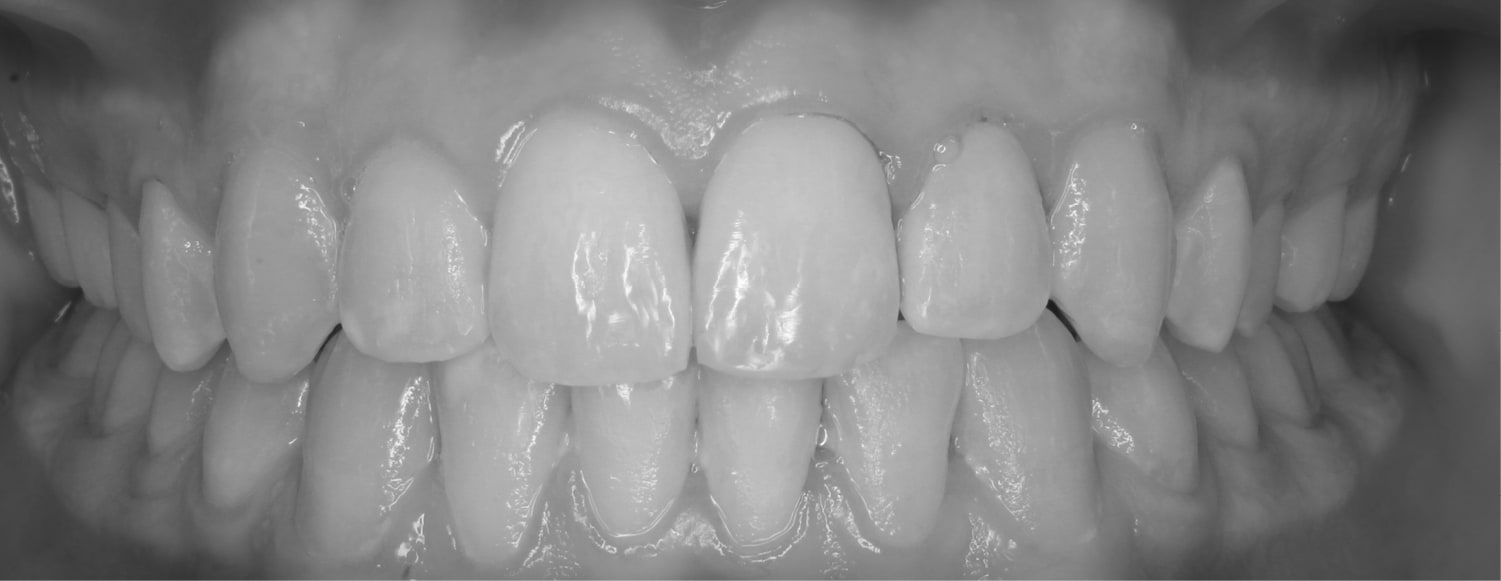

Before

After